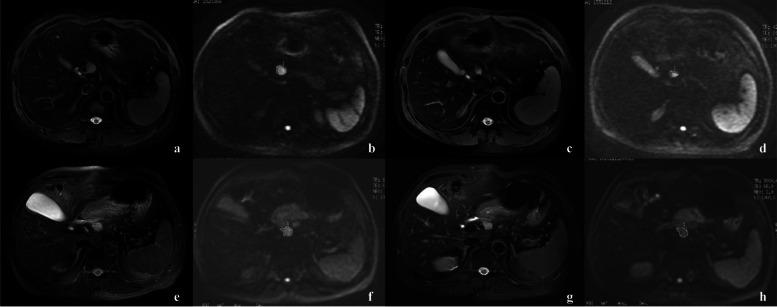

Patients with colorectal liver metastases (CRLM) combined with hepatic lymph node (HLN) metastases have a poor prognosis. In this study, we developed and validated a model using clinical and magnetic resonance imaging (MRI) parameters to predict HLN status before surgery.

A total of 104 CRLM patients undergoing hepatic lymphonodectomy with pathologically confirmed HLN status after preoperative chemotherapy were enrolled in this study. The patients were further divided into a training group (n = 52) and a validation group (n = 52). The apparent diffusion coefficient (ADC) values, including ADC and ADC of the largest HLN before and after treatment, were measured. rADC was calculated referring to the target liver metastases, spleen, and psoas major muscle (rADC, rADC rADC). In addition, ADC change rate (Δ% ADC) was quantitatively calculated. A multivariate logistic regression model for predicting HLN status in CRLM patients was constructed using the training group and further tested in the validation group.

In the training cohort, post-ADC (P = 0.018) and the short diameter of the largest lymph node after treatment (P = 0.001) were independent predictors for metastatic HLN in CRLM patients. The model's AUC was 0.859 (95% CI, 0.757-0.961) and 0.767 (95% CI 0.634-0.900) in the training and validation cohorts, respectively. Patients with metastatic HLN showed significantly worse overall survival (p = 0.035) and recurrence-free survival (p = 0.015) than patients with negative HLN.